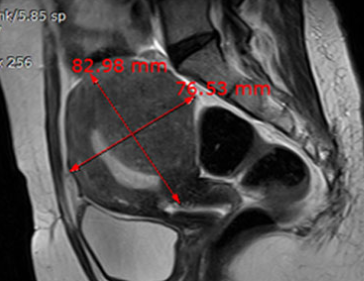

• 시술 전

시술 후